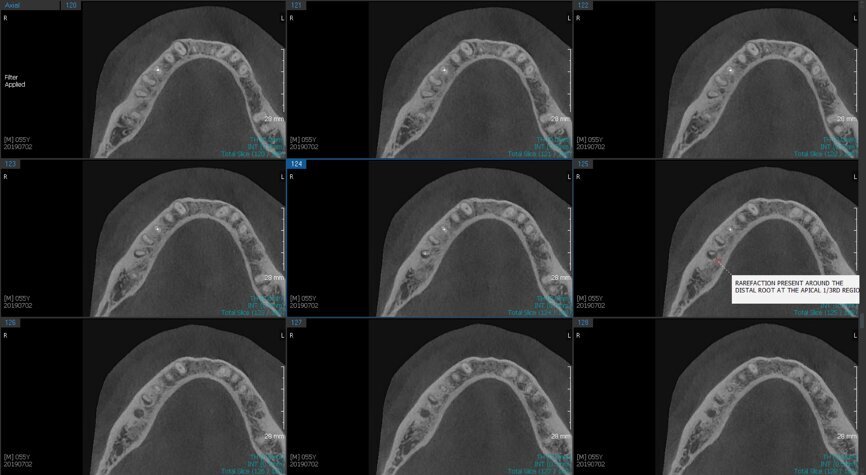

Fig.2a: Pre-op CBCT images of tooth #46: No obturation material in the distal and mesiobuccal canal (a); scanty obturation of the canals and breach of the floor of the pulp chamber, no obturation beyond a few millimetres down the orifice (b & c); radiolucency in the furcation area and periapical region of both roots (d -g).

Fig.2b: Pre-op CBCT images of tooth #46: No obturation material in the distal and mesiobuccal canal (a); scanty obturation of the canals and breach of the floor of the pulp chamber, no obturation beyond a few millimetres down the orifice (b & c); radiolucency in the furcation area and periapical region of both roots (d -g).

Fig.2c: Pre-op CBCT images of tooth #46: No obturation material in the distal and mesiobuccal canal (a); scanty obturation of the canals and breach of the floor of the pulp chamber, no obturation beyond a few millimetres down the orifice (b & c); radiolucency in the furcation area and periapical region of both roots (d -g).

Fig.2d: Pre-op CBCT images of tooth #46: No obturation material in the distal and mesiobuccal canal (a); scanty obturation of the canals and breach of the floor of the pulp chamber, no obturation beyond a few millimetres down the orifice (b & c); radiolucency in the furcation area and periapical region of both roots (d -g).

Fig.2e: Pre-op CBCT images of tooth #46: No obturation material in the distal and mesiobuccal canal (a); scanty obturation of the canals and breach of the floor of the pulp chamber, no obturation beyond a few millimetres down the orifice (b & c); radiolucency in the furcation area and periapical region of both roots (d -g).

Fig.2f: Pre-op CBCT images of tooth #46: No obturation material in the distal and mesiobuccal canal (a); scanty obturation of the canals and breach of the floor of the pulp chamber, no obturation beyond a few millimetres down the orifice (b & c); radiolucency in the furcation area and periapical region of both roots (d -g).

Fig.2g: Pre-op CBCT images of tooth #46: No obturation material in the distal and mesiobuccal canal (a); scanty obturation of the canals and breach of the floor of the pulp chamber, no obturation beyond a few millimetres down the orifice (b & c); radiolucency in the furcation area and periapical region of both roots (d -g).

When I had a close look at the preoperative radiograph from the referring dentist (Fig. 1a), I observed that there was insufficient obturation of the mesial canals and almost no obturation of the distal canal. Both roots displayed periapical radiolucency. The clinical examination revealed a Grade I mobility, and the tooth was tender to percussion. The periodontal examination ruled out any pockets and loss of attachment. We took an intra-oral periapical radiograph (Fig. 1b), from which we observed the loss of coronal structure and a large radiolucent area over the furcation area and the periapical area of both the mesial and the distal roots. A CBCT scan of tooth #46 was advised to check for any details that may have been missed in the intra-oral periapical radiograph (Figs. 2a–g). From the CBCT scan, it could be observed that there was inadequate obturation of the distal canal on the horizontal plane, no obturation beyond the middle third in the mesial canals and a breach of the floor of the pulp chamber. The questionable prognosis was explainedto the patient, and written consent was obtained.